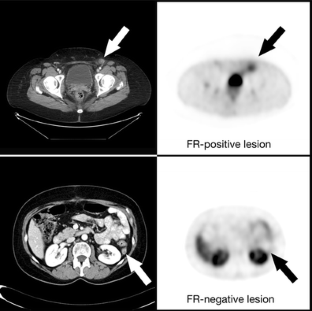

Fig. 3

63. Morris, R. T., Joyrich, R. N., Naumann, R. W., Shah, N. P., Maurer, A. H., Strauss, H. W., et al. (2014). Phase 2 study of treatment of advanced ovarian cancer with folate-receptor-targeted therapeutic (vintafolide) and companion SPECT-based imaging agent (99mTc-etarfolatide). Annals of Oncology, 25(4), 852–858.

CAS  Article  PubMed  Google Scholar